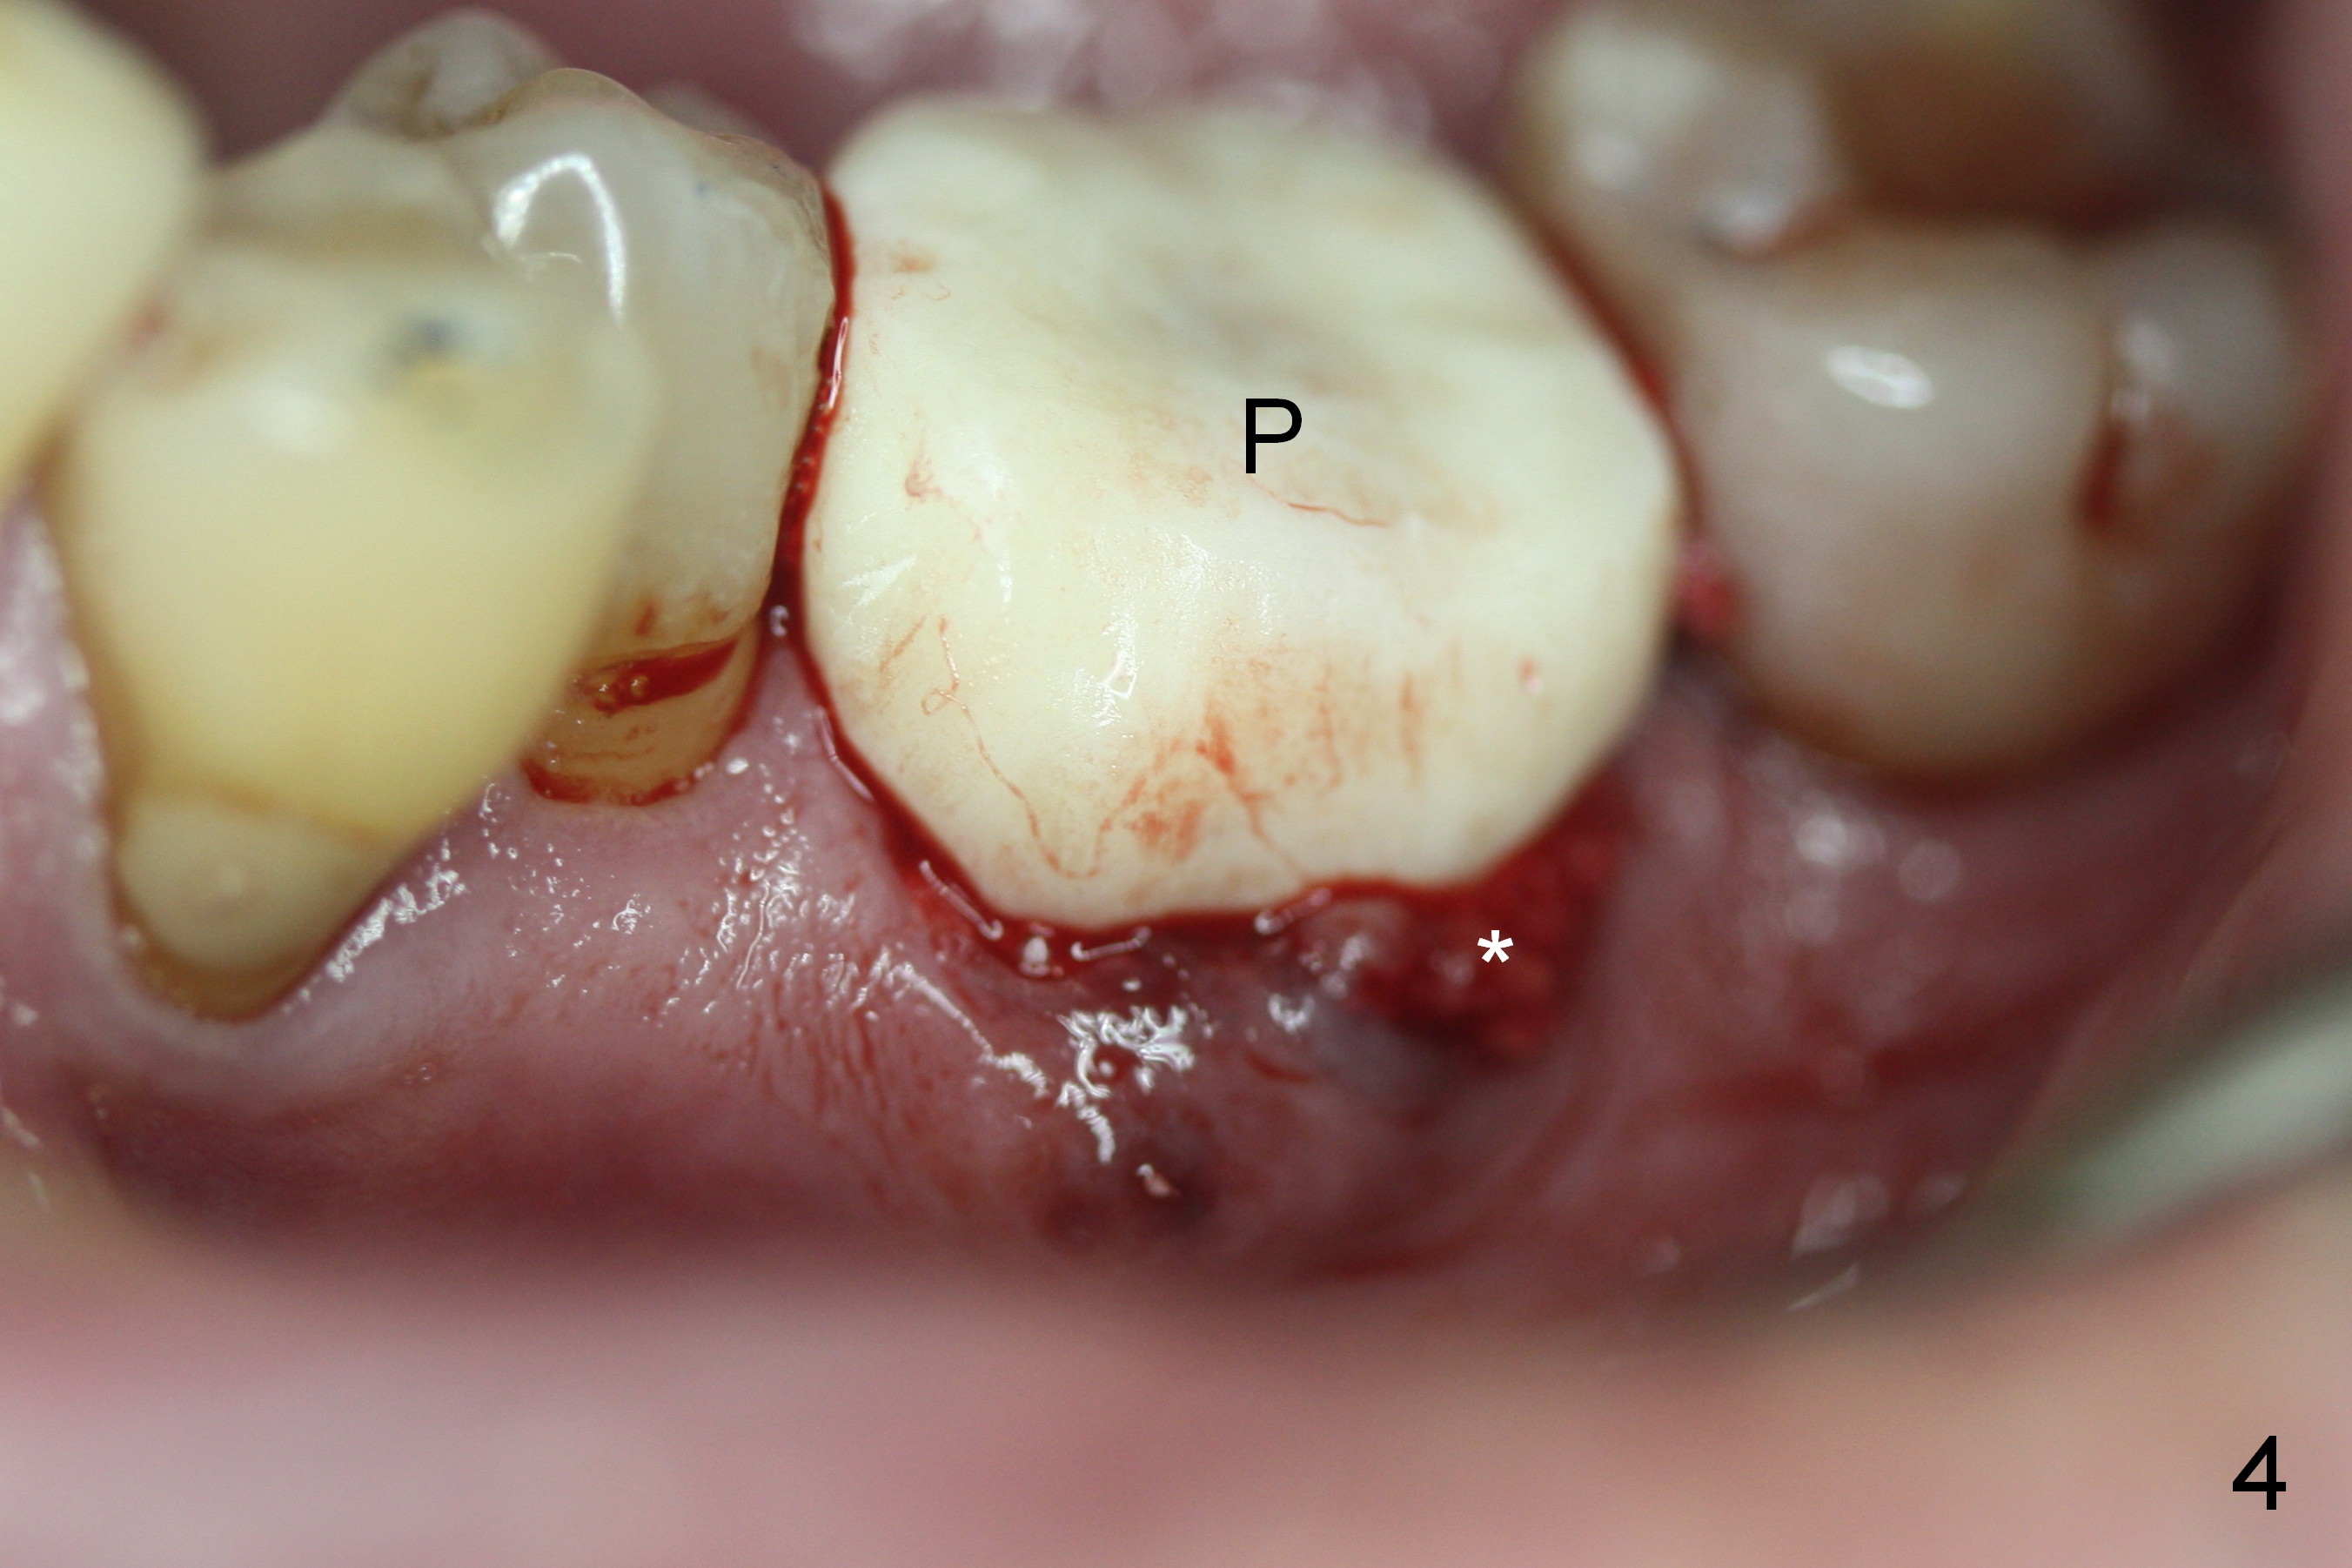

A fistula is found to be associated with the furca when the patient returns for extraction (Fig.1 <). Although the mesial socket is deeper than the distal one, no granulation tissue is curetted from the mesial. Osteotomy is set in the middle of the septum by making a slot first. When the osteotomy is enlarged by 4 mm reamer (Fig.2 R), the latter has been deviated mesial to the septum (*). By manipulating, the coronal end of 6x12 mm implant and 6.5x4(3) mm abutment (Fig.3 A) are placed somewhat in the middle of the socket. An immediate provisional is fabricated to cover the socket and bone graft (Fig.4 P). The exposed bone graft (Fig.4 *) is then covered by perio dressing. Off axial placement of the implant (Fig.5 I) and abutment (A) is striking in the immediately postop PA (Fig.5).